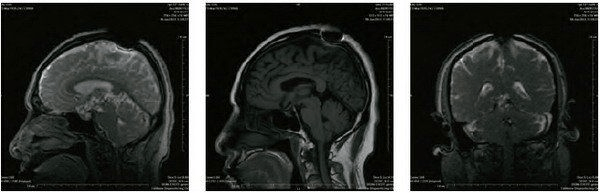

KaiChu Rinpoche MRI magnetic resonance imaging brain CT scan medical images